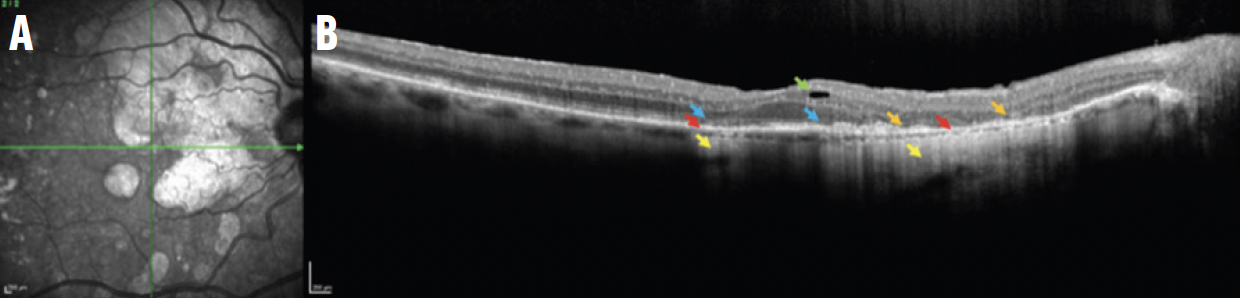

Рис. 3. NIR зображення (A) та В-скан ОКТ iRORA ураження (B) відображають порушення ELM та EZ (сині стрілки) та вогнищеве зменшення RPE (червона стрілка) з гіпертрансмісією в хоріоїдею (жовта стрілка).